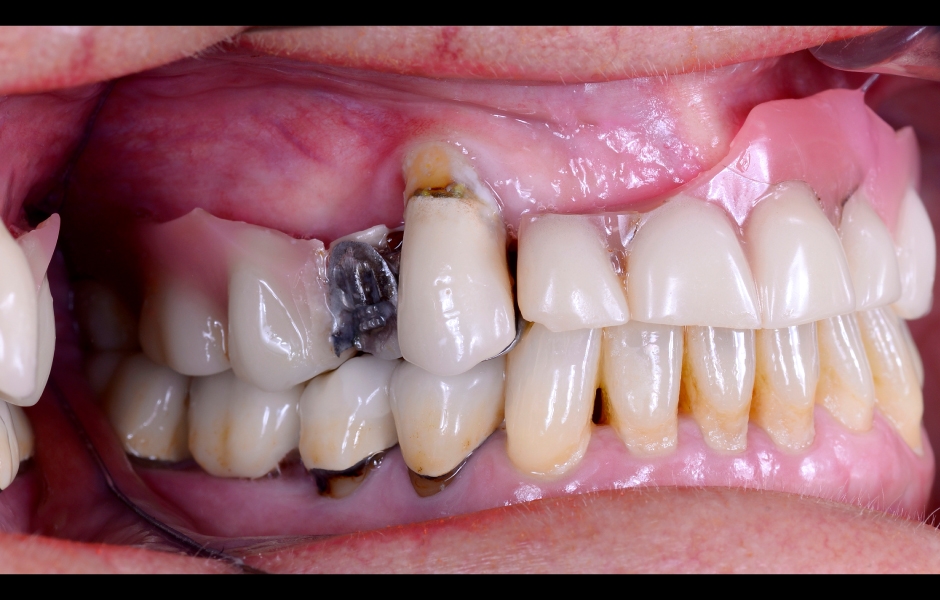

V prezentovaném případě byla k implantoprotetické rehabilitaci odeslána téměř 78letá pacientka, bývalá silná kuřačka. V průběhu let přišla v důsledku generalizované chronické parodontitidy o všechny zuby v horní čelisti, s výjimkou zubu 13, který byl výrazně kompromitovaný, viklavý a bez možnosti záchrany. Pacientka si stěžovala na přetrvávající krvácení, citlivou sliznici horní čelisti a halitózu. Její hlavní prioritou bylo mít „co nejdříve fixní zuby“, aby mohla konečně bez bolesti kousat a usmívat se.

Pacientka proto souhlasila s léčebným plánem zahrnujícím okamžitou podmíněně fixní rekonstrukci nesenou šesti implantáty copaSKY (bredent medical). V dolní čelisti byla naplánována kompletní dezinfekce ústní dutiny s cílem udržet mikrobiální zátěž kolem zbývajících zubů co nejnižší (obr. 1–4).

Obr. 1: Klinická a radiologická výchozí situace v horní čelisti se selhávajícími předchozími rekonstrukcemi.

Obr. 2: Klinická a radiologická výchozí situace v horní čelisti se selhávajícími předchozími rekonstrukcemi.

Obr. 3: Klinická a radiologická výchozí situace v horní čelisti se selhávajícími předchozími rekonstrukcemi.

Obr. 4: Klinická a radiologická výchozí situace v horní čelisti se selhávajícími předchozími rekonstrukcemi.